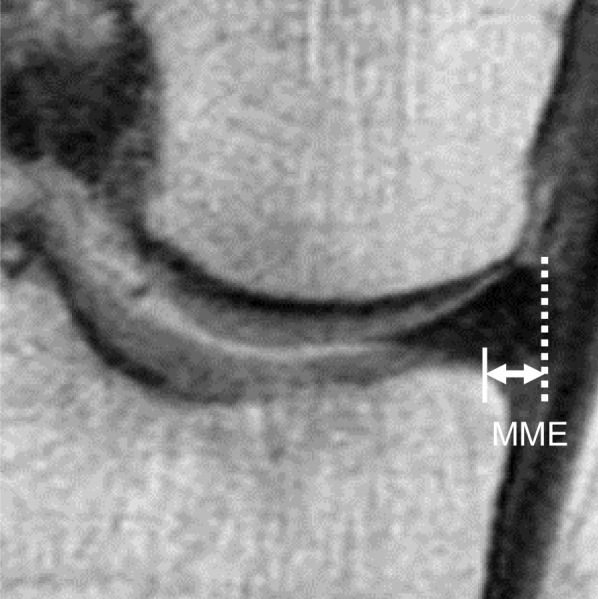

Materials and methods: We retrospectively evaluated 15 consecutive patients (male/female, 5/10; average age, 64.4 years) who underwent transtibial pullout repair for partial medial meniscus posterior root tears and compared their results with those of 86 consecutive patients who underwent the same surgery for complete medial meniscus posterior root tears. All patients underwent second-look arthroscopy on average 1 year postoperatively, and a semi-quantitative meniscal healing score (anteroposterior width, stability, and synovial coverage, total 10 points) was evaluated. Medial meniscus extrusion was evaluated preoperatively and at second-look arthroscopy.

Results: Postoperative clinical scores were not significantly different in the short term. However, second-look arthroscopy revealed a significant difference in repaired meniscal stability (partial tear; 3.3 points, complete tear; 2.3 points, p < 0.001) and total meniscal healing scores (partial tear; 8.3 points, complete tear; 7.1 points, p < 0.001). Medial meniscus extrusion progression was significantly different (partial tear; 0.4 mm, complete tear; 1.0 mm, p < 0.001).

Conclusion: Partial medial meniscus posterior root tears showed better meniscal healing and less medial meniscus extrusion progression following pullout repair than complete medial meniscus posterior root tears.